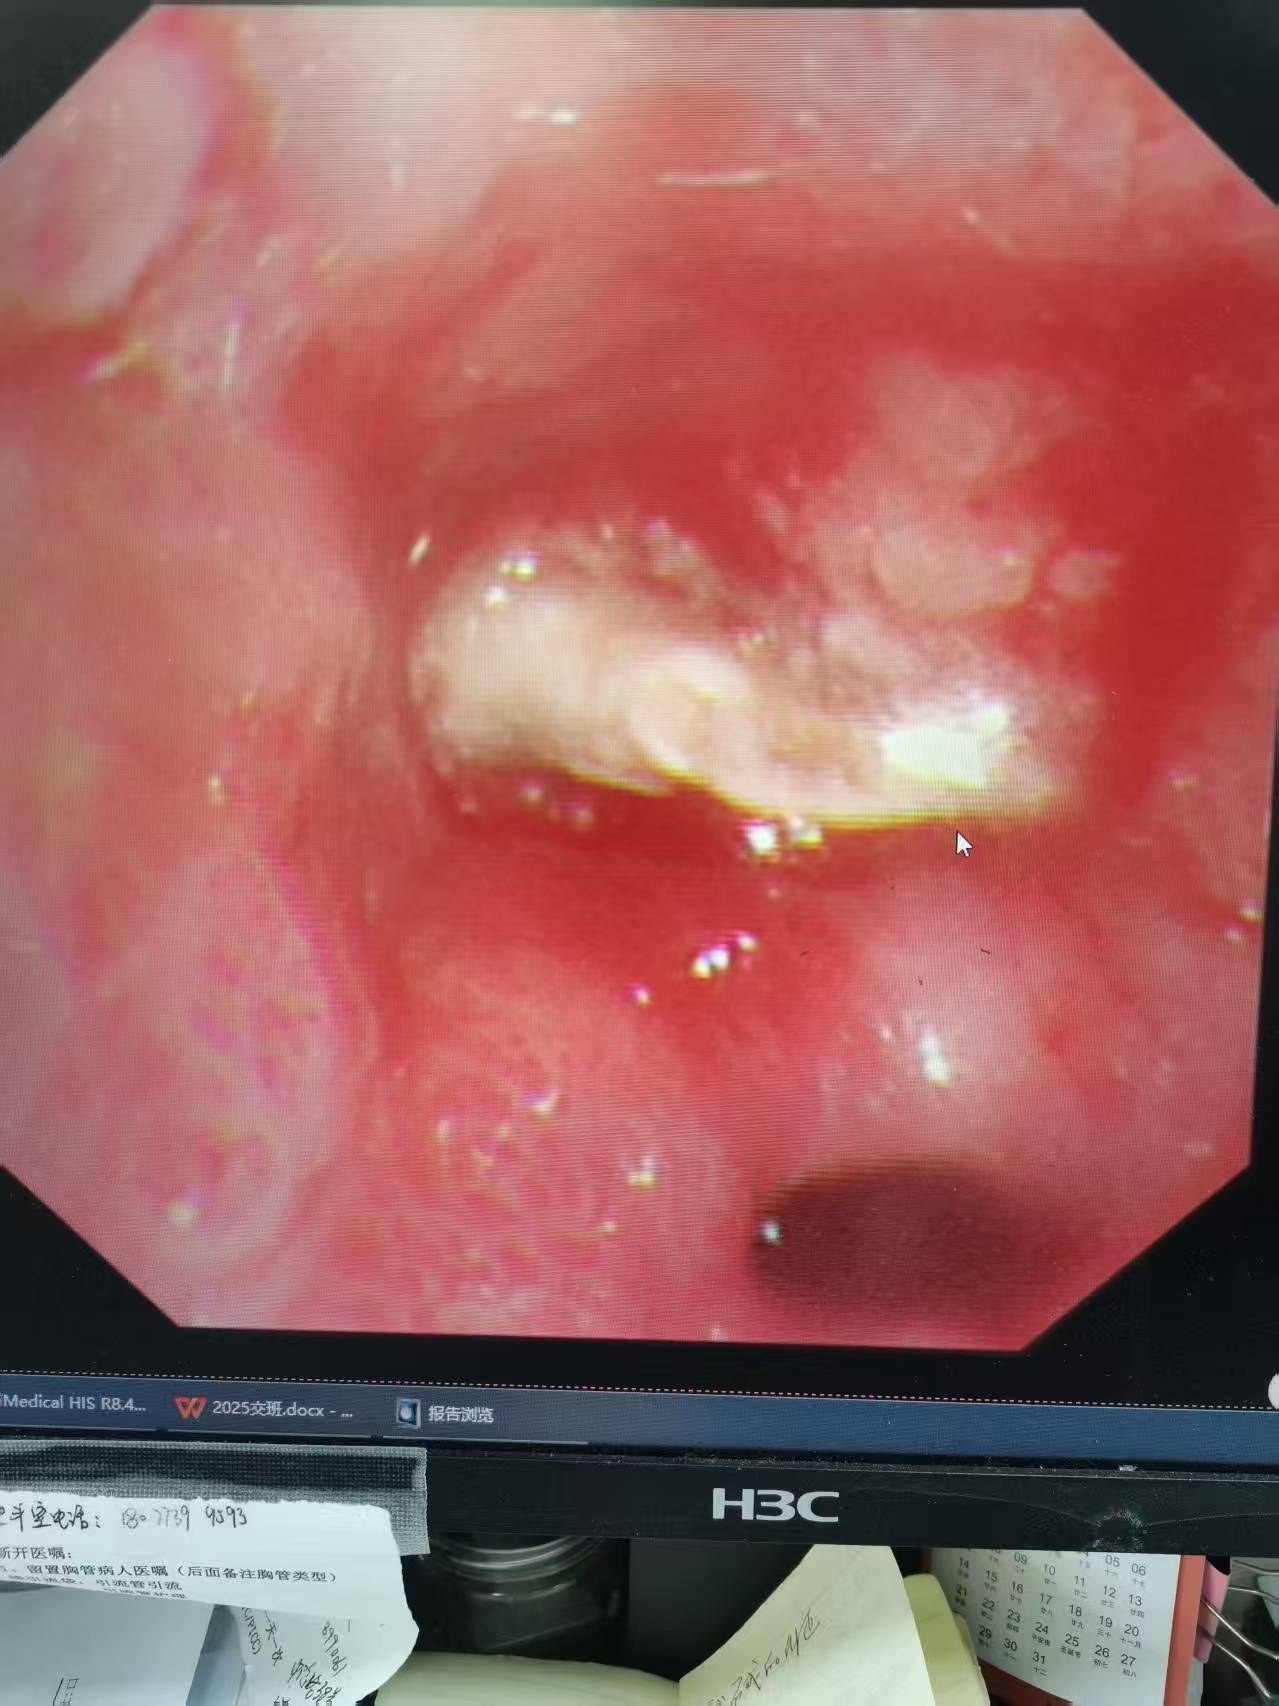

(图1:支气管镜下清晰可见右下叶开口处异物嵌顿,周围粘膜充血水肿。)

面对这一棘手情况,佘巍巍主任团队展现了高度的专业负责精神与精准的研判能力。 团队没有局限于常规治疗,而是深入分析病情特点,考虑到气道异物可能性,耐心与患者及家属沟通,最终说服患者接受关键性的支气管镜检查。检查过程中,团队操作细致精准, 迅速于右下叶支气管开口处发现了嵌顿的异物及周围显著炎症,一举揭开了困扰患者多时的病因谜团。